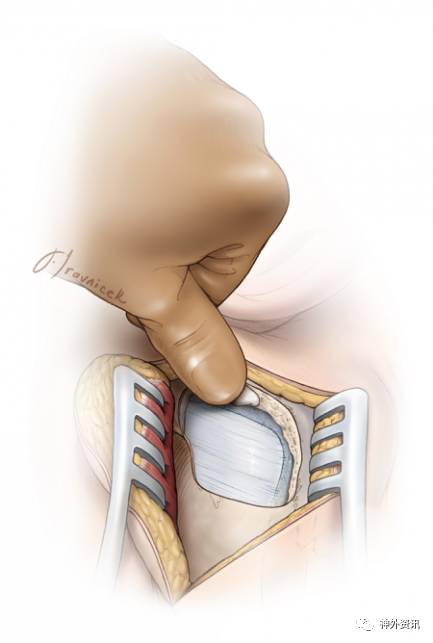

图11. 扩大乙状窦后入路:裸露后半部分乙状窦是该入路获得更大术野的关键步骤。

掀起骨瓣后,磨除部分乳突,显露乙状窦全长的后份。同时,去除外侧的乳突骨板和任何阻挡骨质使乙状窦可随硬膜往前翻转。因此,可能对小脑的牵拉减轻了,但是从前外侧方观察桥小脑角的视野增加了,术者的操作角度也更灵活。

移除乙状窦表面的骨质时,最佳方法是使用磨钻的“蛋壳化”技术,因为两者之间常常粘连紧密。钻头与钻柄的移动方向保持一致,以免误伤。